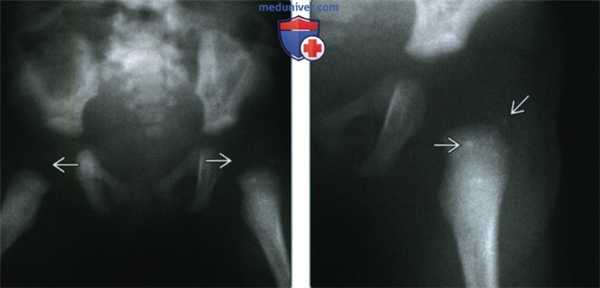

(Слева) Рентгенография таза в ПЗ проекции, выполненная у новорожденного. Отсутствие оссификации эпифиза головки бедренной кости указывает на задержку развития скелета. Выявление этого признака и его связь с гипотиреозом имеют ключевое значение в предотвращении осложнений этих заболеваний.

(Справа) Рентгенография левого тазобедренного сустава в ПЗ проекции, этот же пациент: определяется точечная дисплазия апофиза большого вертела - в этом случае не выраженная. Точечная дисплазия эпифизов - характерный симптом гипотиреоза. (Слева) Рентгенография таза в ПЗ проекции у четырехлетнего ребенка: определяется фрагментация эпифиза головки бедренной кости (обозначается термином «кретиноидное бедро»). Отмечается расширение пластинок роста в обоих тазобедренных суставах. Данные указывают на задержку развития скелета.